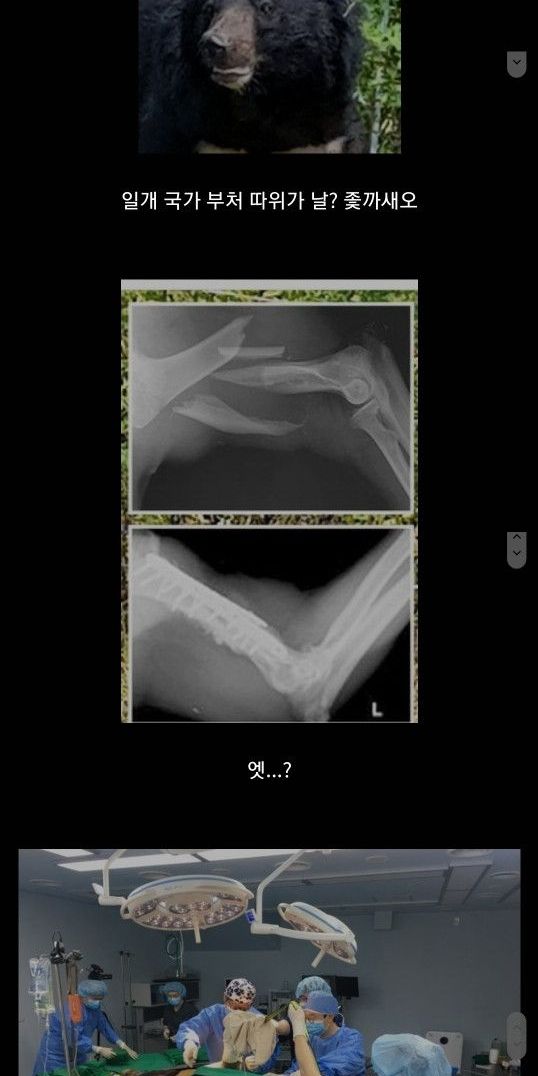

지리산은 야생 동물들의 서식지로도 잘 알려져 있습니다. 특히 지리산에 서식하는 반달가슴곰은 환경보호의 상징적인 동물 중 하나입니다. 이 곰들은 지리산의 생태계를 건강하게 유지하는데 중요한 역할을 합니다.

반달가슴곰은 지리산의 대표적인 야생동물로, 반달 모양의 흰털이 가슴 부분에 있어 이름이 붙여졌습니다. 이들은 지리산 생태계의 균형을 유지하며, 멸종 위기종으로 보호받고 있습니다. 다양한 보전 활동과 연구가 진행되어 곰들이 안전하게 서식할 수 있는 환경이 조성되고 있습니다.